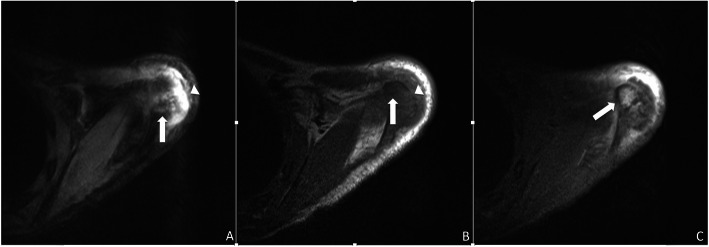

Fig. 4.

Left shoulder MRI axial images demonstrate signal characteristics consistent with osteomyelitis at the acromial apophysis: hyperintense (brighter) on T2 weighted imaging (a) and hypointense (darker) on T1 weighted imaging (b) with contrast enhancement on post-gadolinium T1 weighted imaging with fat suppression (white arrow c). Cortical disruption (arrowhead b) and an overlying fluid collection (arrowhead a) are also present